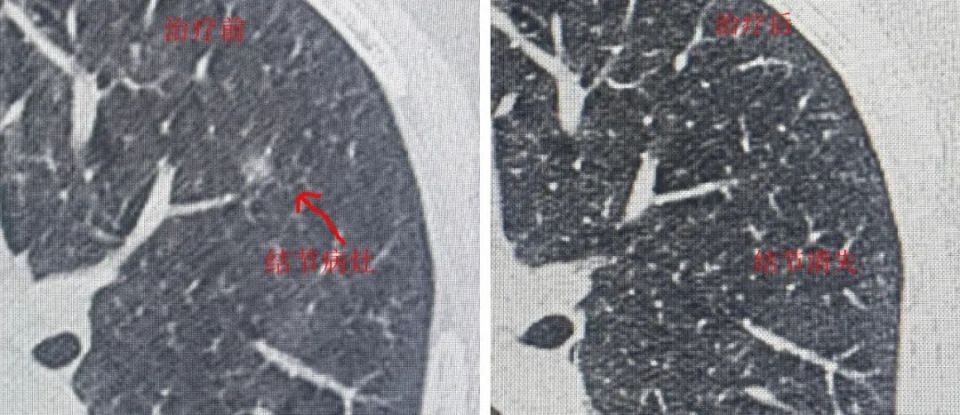

肺部结节也是常见病,随着检查手段的进步,许多很小的结节在体检中被发现。陈志斌认为,肺结节在中医看来,发病原因复杂,但气滞血瘀、气虚痰阻是一部分病人的主要病机。根据这个原则,他发明了一个“肺部阴影方”,经过多年的临床实践,取得了一定的成效,使一些病人免除了手术的痛苦,也为中医治疗肺结节病探索出一条新路。

患者杨某,就诊号:D378761,患肺结节,经陈主任应用“肺部阴影方”治疗三个月后,结节完全消失。